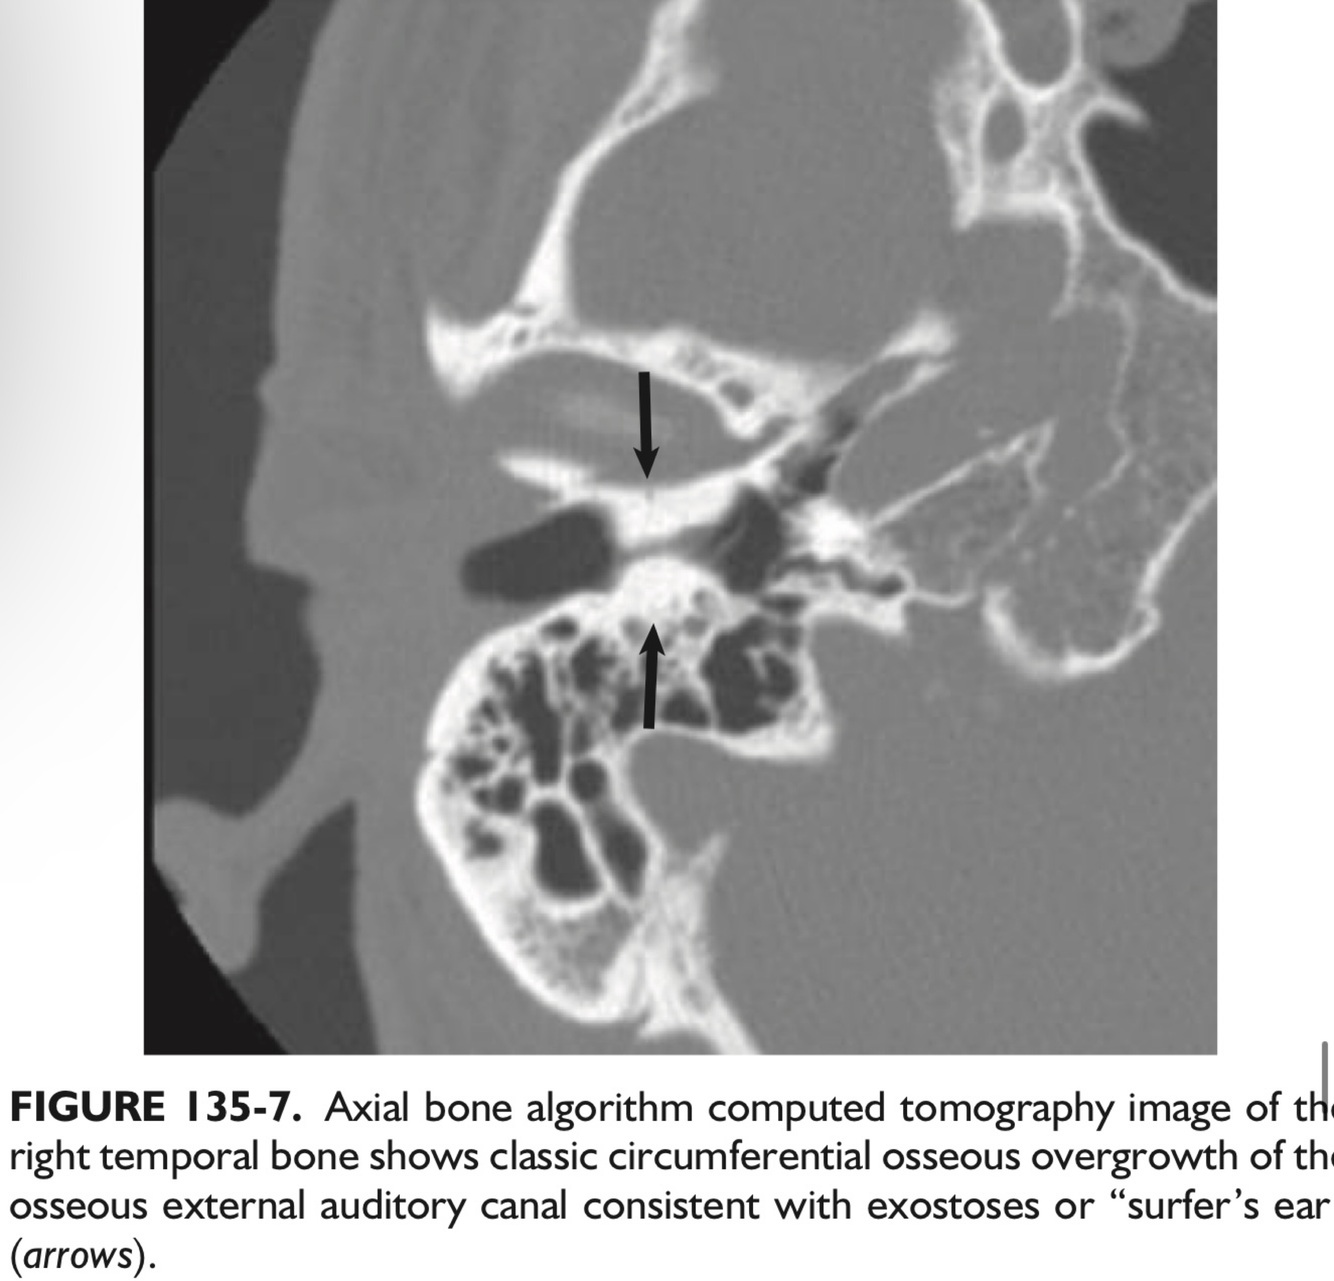

Q

_____, a benign neoplasm of the EAC, are known as “surfer’s ear” frequently seen on imaging in some regions where cold water swimming is common.

They are almost always ___ and typically occur at the ___.

A

Exostoses.

Bilateral, and typically occur at the suture lines.